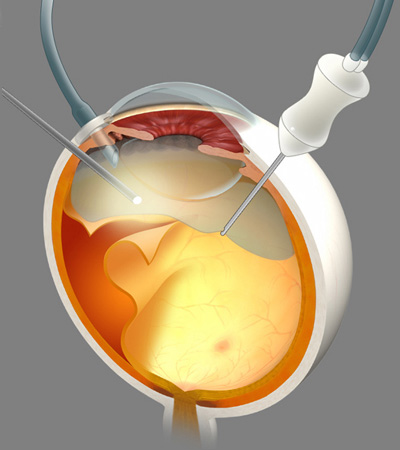

手術の流れは上記の図の通りです。

硝子体手術は眼の奥の様々な病気に対し行われる手術で、眼科領域では最も高度な技術を要する手術です。現在では様々な手術装置や手術技術の発展により手術の安全性は高まっています。。

当院の硝子体手術器具はアルコン社製のコンステレーションを使用しています。コンステレーションの導入により、より安全で確実な手術をおこなえるようにしており、創口が0.5mmと小さい切開を白目にあけるだけの硝子体手術を行っています。

また広角観察システムの導入により、手術時に従来のレンズなら網膜の一部分を見ながらの手術だったのが、全体を把握できるようになり安全な手術ができるようにしています。